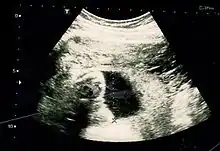

The result of an ultrasonography: a black and white image that shows a clear view of the interior abdomen

Obstetric ultrasonography is routinely used for dating the gestational age of a pregnancy from the size of the fetus, determine the number of fetuses and placentae, evaluate for an ectopic pregnancy and first trimester bleeding, the most accurate dating being in first trimester before the growth of the foetus has been significantly influenced by other factors.[22] Ultrasound is also used for detecting congenital anomalies (or other foetal anomalies) and determining the biophysical profiles (BPP), which are generally easier to detect in the second trimester when the foetal structures are larger and more developed.[23]

X-rays and computerized tomography (CT) are not used, especially in the first trimester, due to the ionizing radiation, which has teratogenic effects on the foetus.[24] No effects of magnetic resonance imaging (MRI) on the foetus have been demonstrated,[25] but this technique is too expensive for routine observation. Instead, obstetric ultrasonography is the imaging method of choice in the first trimester and throughout the pregnancy, because it emits no radiation, is portable, and allows for realtime imaging.[26]

The safety of frequent ultrasound scanning has not been confirmed. Despite this, increasing numbers of women are choosing to have additional scans for no medical purpose, such as gender scans, 3D and 4D scans.[27] A normal gestation would reveal a gestational sac, yolk sac, and fetal pole.[28]

The gestational age can be assessed by evaluating the mean gestational sac diameter (MGD) before week 6, and the crown-rump length after week 6. Multiple gestation is evaluated by the number of placentae and amniotic sacs present.[29]